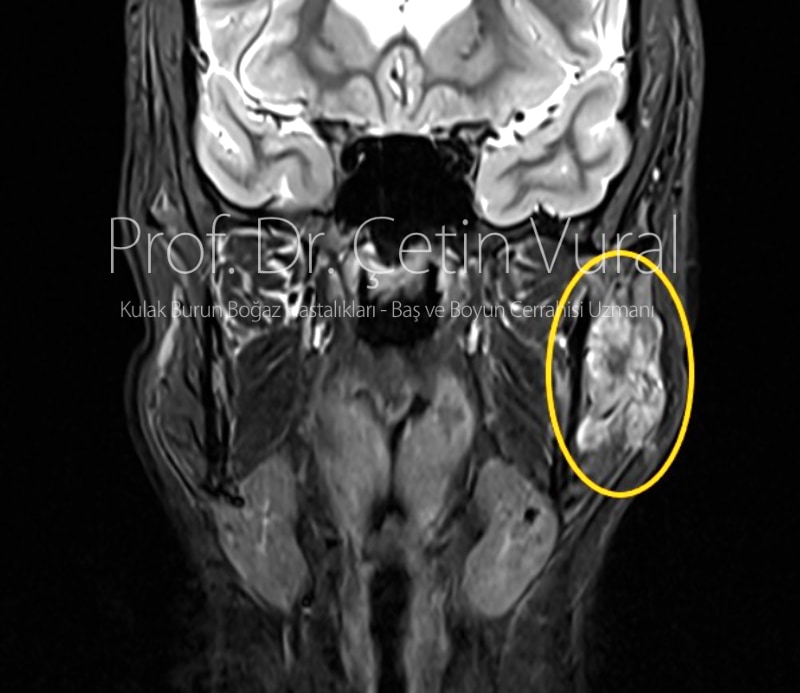

Bu kitleden 2020 yılında iğne biyopsisi ile örnek alınmış ve sonuç “önemi belirsiz atipi” olarak raporlanmış. Hastaya yapılmış olan MR incelemede sol parotis bezine yerleşmiş tümörün, sol tarafta çeneyi kapatan kaslara da uzandığı görülmekteydi. Bu nedenle kalın iğne biyopsisi yapıldı ve sonuç Malign Epitelyal Tümör, “kitlenin tamının çıkartılması önerilir.” olarak raporlandı.